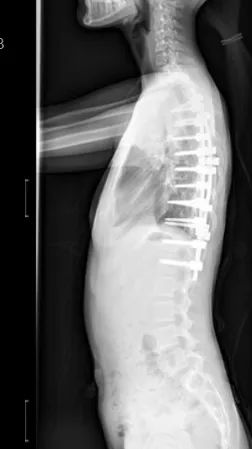

▲ 女,12岁,特发性脊柱侧凸、先天性脊柱畸形

▲ 女,14岁,青少年特发性脊柱侧凸